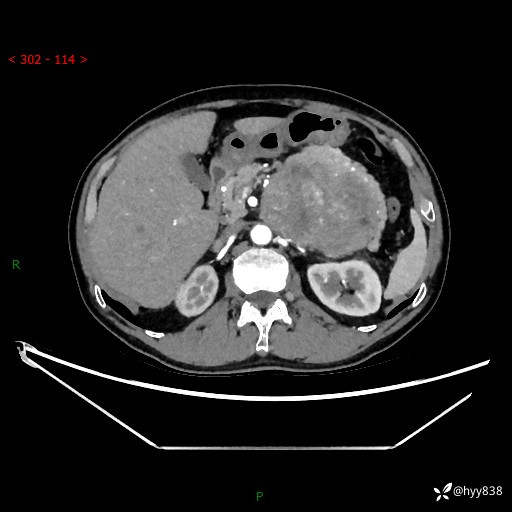

年龄:61岁

主诉:发现腹膜后肿瘤3天

腹部CT平扫+增强(动脉期+静脉期)